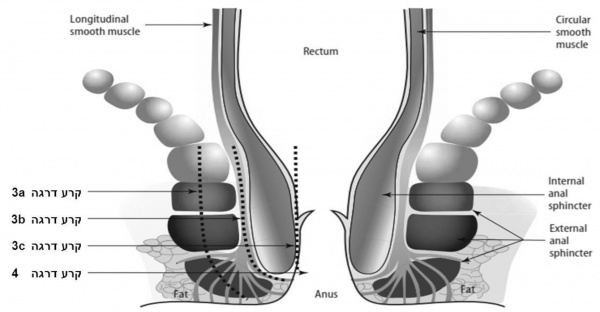

אנטומיה

תעלת פי הטבעת (Anal canal) מוקפת על ידי שני שרירים טבעתיים ואורכה כ־3 - 3.5 ס"מ מהפתח. שרירים אלה מהווים סוגר למניעת דליפה לא רצונית של צואה. השריר IAS (Internal anal sphincter) הוא עיבוי דיסטלי המשכי של השריר החלק המעגלי העוטף את המעי הגס. הוא אחראי לכ־70% מהלחץ הבסיסי של הסוגר ונמצא תחת שליטה של עצבוב אוטונומי. השריר (External anal sphincter (EAS הוא שריר משורטט, העוטף את השריר IAS ואחראי לכיווץ הרצוני ולכ־30% מהלחץ הבסיסי של הסוגר. השריר EAS מעוצבב על ידי Pudendal nerve[2].

הסיווג המקובל של קרעים בחיץ הנקבים תואר לראשונה על ידי Sultan וחב' ואומץ על ידי RCOG (Royal College of Obstetrics and Gynecology) [1][7]. (ראו תמונה 1).

- טבלה 1

| ללא קרע | חיץ-הנקבים שלם. | |

| קרע דרגה 1 | קרע בעור חיץ-הנקבים בלבד. | |

| קרע דרגה 2 | קרע בחיץ-הנקבים המערב את השרירים השטחיים אך לא את שרירי הסוגר של פי הטבעת. | |

| קרע דרגה 3 | קרע בחיץ-הנקבים המערב שרירי הסוגר של פי הטבעת הסוגר בדרגות שונות: | |

| קרע 3a | קרע המערב את שריר הסוגר החיצון (EAS) בעומק הקטן ב-50% מעוביו. | |

| קרע 3b | קרע המערב את שריר הסוגר החיצון (EAS) בעומק הגדול ב-50% מעוביו. | |

| קרע 3c | קרע המערב את שריר הסוגר החיצון ושריר הסוגר הפנימי (EAS ו- IAS) | |

| קרע דרגה 4 | קרע בחיץ-הנקבים המערב שרירי הסוגר של פי הטבעת הסוגר (EAS ו- IAS) ואת רירית האנוס. | |